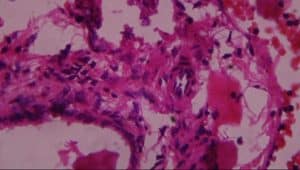

Figure 13: Rat given Pb Acetate + Silymarin showing: A-normal hepatocytes and B-kupffer cell activation (H&E x 100)

By extension, a highly expensive drug called Silymarin, a known drug used in the treatment of liver disease with an undetected actual mechanism of action according to literature and web, showed the similar ameliorative effect of aqueous extract of L. inermis; the architecture of the liver was reverted to normal with the activation of Kupffer cells.[32] This attenuated effect was also in accordance with the same work done by dos Reis and colleagues.[32] That shows that Silymarin attenuates the adverse effects of damage to the liver, showing less extensive steatosis and necrosis.